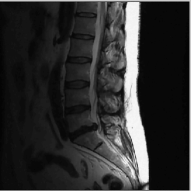

Finally, we show the recovery of four MR images from three fold radial under sampled data that is contaminated with zero mean complex Gaussian noise of standard deviation σ=10𝜎10\sigma=10. These experiments show that the NLS scheme can be used to obtain good quality reconstructions at moderate acceleration factors and noise levels.

Figure 7: Comparison of different MR images using NLS algorithms in the presence of noise. We consider the recovery from a three fold undersampled radial sampling pattern, contaminated by zero mean complex Gaussian noise with standard deviation σ=10𝜎10\sigma=10. The top two rows show the original and reconstructed images, while the error images scale by a factor of five are shown in the bottom row. We observe that the NLS scheme preserves well the edges and the fine details at low acceleration with presence of noise.